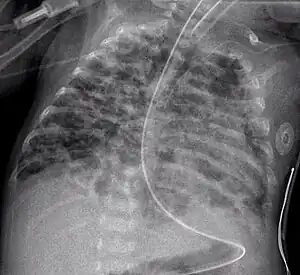

In anteroposterior (AP) views, the positions of the x-ray source and detector are reversed: the x-ray beam enters through the anterior aspect and exits through the posterior aspect of the chest. AP chest x-rays are harder to read than PA x-rays and are therefore generally reserved for situations where it is difficult for the patient to get an ordinary chest x-ray, such as when the patient is bedridden. In this situation, mobile X-ray equipment is used to obtain a lying down chest x-ray (known as a "supine film"). As a result, most supine films are also AP.